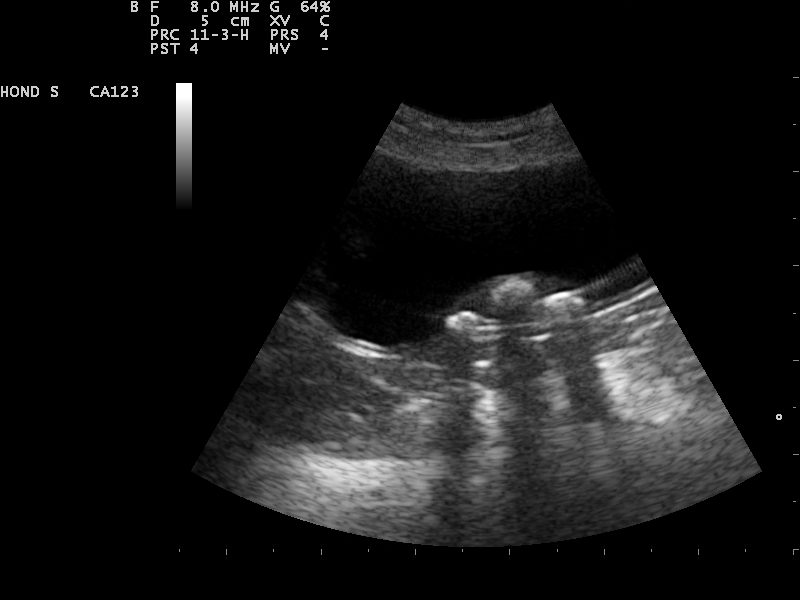

Hierbij zat ook een scoop, om in de blaas van een teefje te kunnen kijken. Op deze manier konden we de blaasstenen met de scoop verwijderen en zo een buikoperatie vermijden.

De behandeling viel voor onze dierenarts uiteindelijk wel wat tegen. Niet omdat het verwijderen van de blaasstenen via de scoop niet lukte, maar omdat er zo ontzettend veel blaassteentjes aanwezig bleken te zijn.

Het verwijderen van de blaassteentjes verliep soepel met behulp van allerlei grijpertjes.